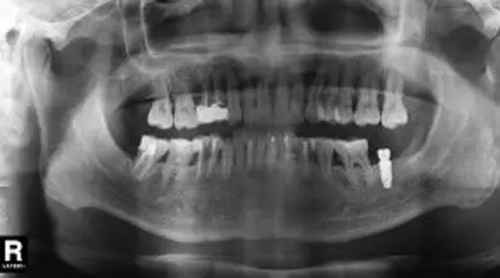

圖6 拔除47前曲面體層片

臨床檢查47面見大面積充填物,冠近遠(yuǎn)中折裂,叩痛(+),松動(dòng)度(-),牙齦(-)。曲面體層片示46髓腔內(nèi)及根管見高密度影像,根尖未見明顯陰影(圖6)。